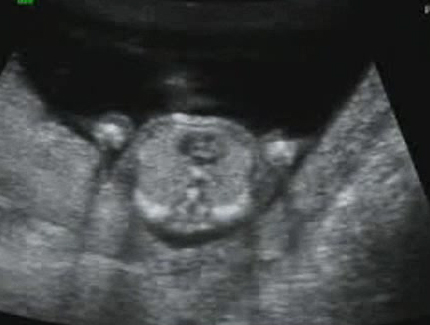

因此這回超音波,

有特地給我一張手和一張腳的照片,

下面照片是屁股往上拍。

沒記錯兩邊小圈是腳,

上面一個灰灰小影是頭在動來動去!

可以對照影片裡的部分。